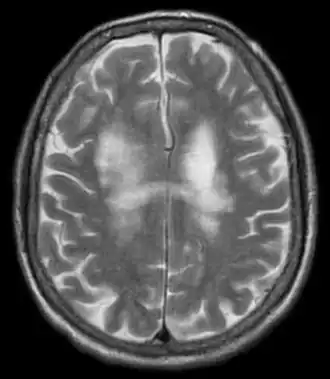

Progressieve multifocale leukencefalopathie (PML)[1] is een zeldzame, progressief verlopende demyeliniserende aandoening van het centrale zenuwstelsel die meestal overlijden of ernstige invaliditeit tot gevolg heeft.